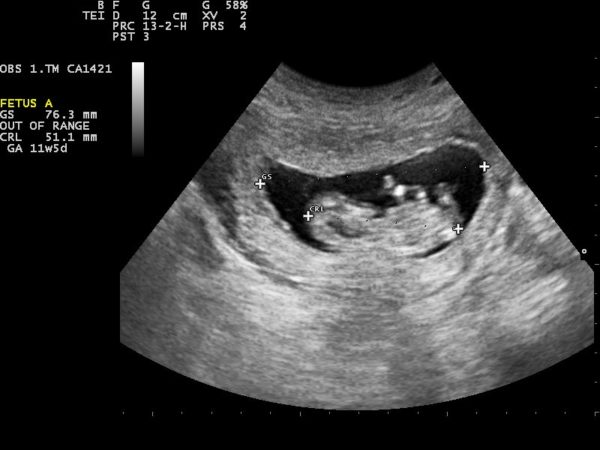

Siêu âm có túi thai nhưng chưa thấy phôi thai có sao không? (Ảnh minh họa)

Việc siêu âm có túi thai nhưng chưa thấy phôi thai ở tuần thứ 5 là bình thường (Ảnh minh họa)